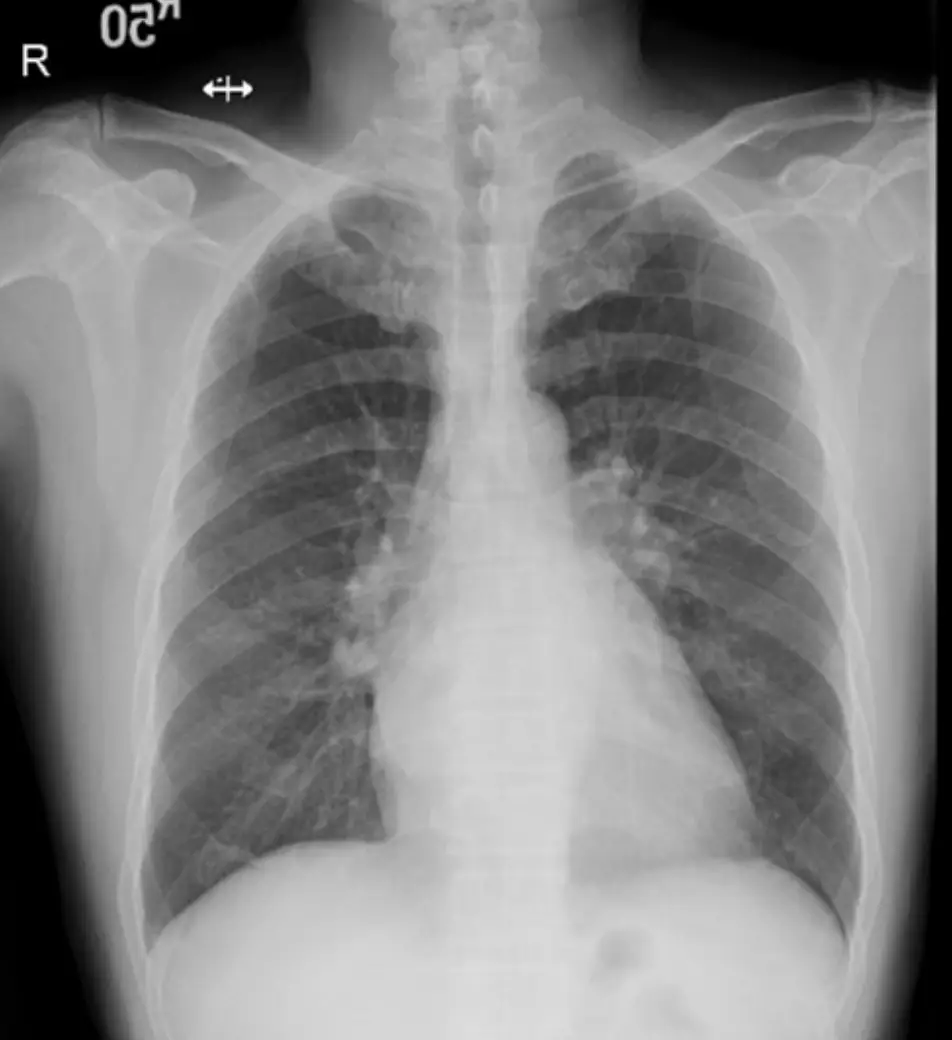

- 胸部 X 光:心影並未明顯增大,但左心房輪廓可見輕度放大(左側上縱隔輕度隆起),肺野清晰無水腫或淋巴管暈狀改變,提示肺循環壓力尚未嚴重失代償。